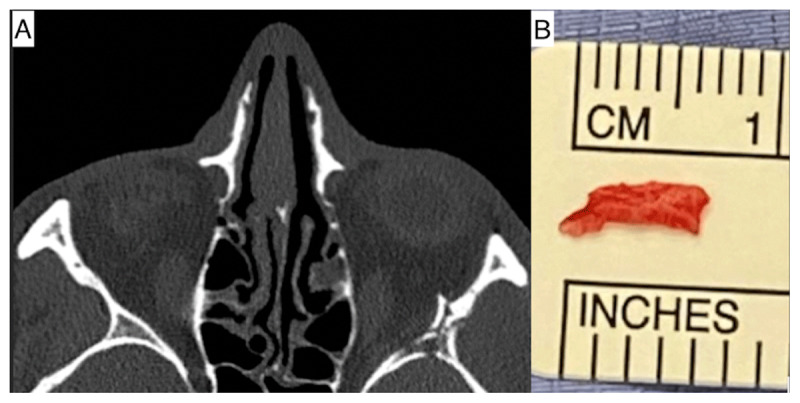

Case report: A 29-year-old male reported falling 15 feet. He presented with diplopia and had complete abduction deficit of the left eye. Orbital CT imaging revealed a bony spur from his left zygomatic bone impinging on the lateral rectus muscle. In view of -4 abduction deficit, he was operated upon to remove the bony spur. This led to a gradual, but complete recovery of his abduction.